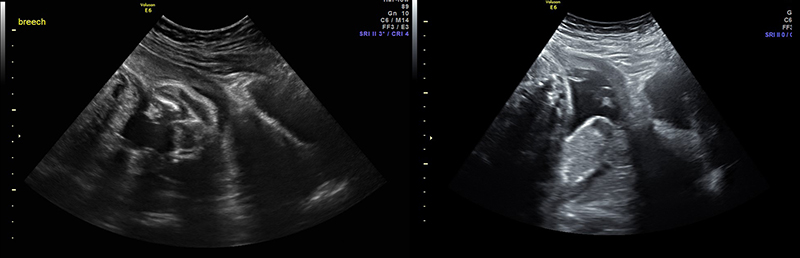

- Non-vertex (breech, transverse, or oblique) increases risk of difficult delivery and complication25

Figures 30A & B. Suprapubic views revealing no fetal cranium in the pelvis. While in some cases like this transverse view of a breech presentation (A) and this sagittal view of a transverse presentation (B), it may be difficult to exactly determine the fetal anatomy, the lack of the fetal cranium is adequate to rule out a vertex presentation and should increase the clinician’s suspicion for a more difficult delivery.